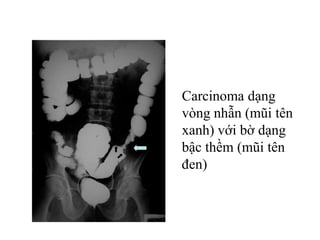

Carcinoma dạng

vòng nhẫn (mũi tên

xanh) với bờ dạng

bậc thềm (mũi tên

đen)

Carcinoma đại

tràng dạng polyp

Carcinoma dạng vòng nhẫn(mũi tên xanh) với bờ dạng bậc thềm (mũi tên đen)